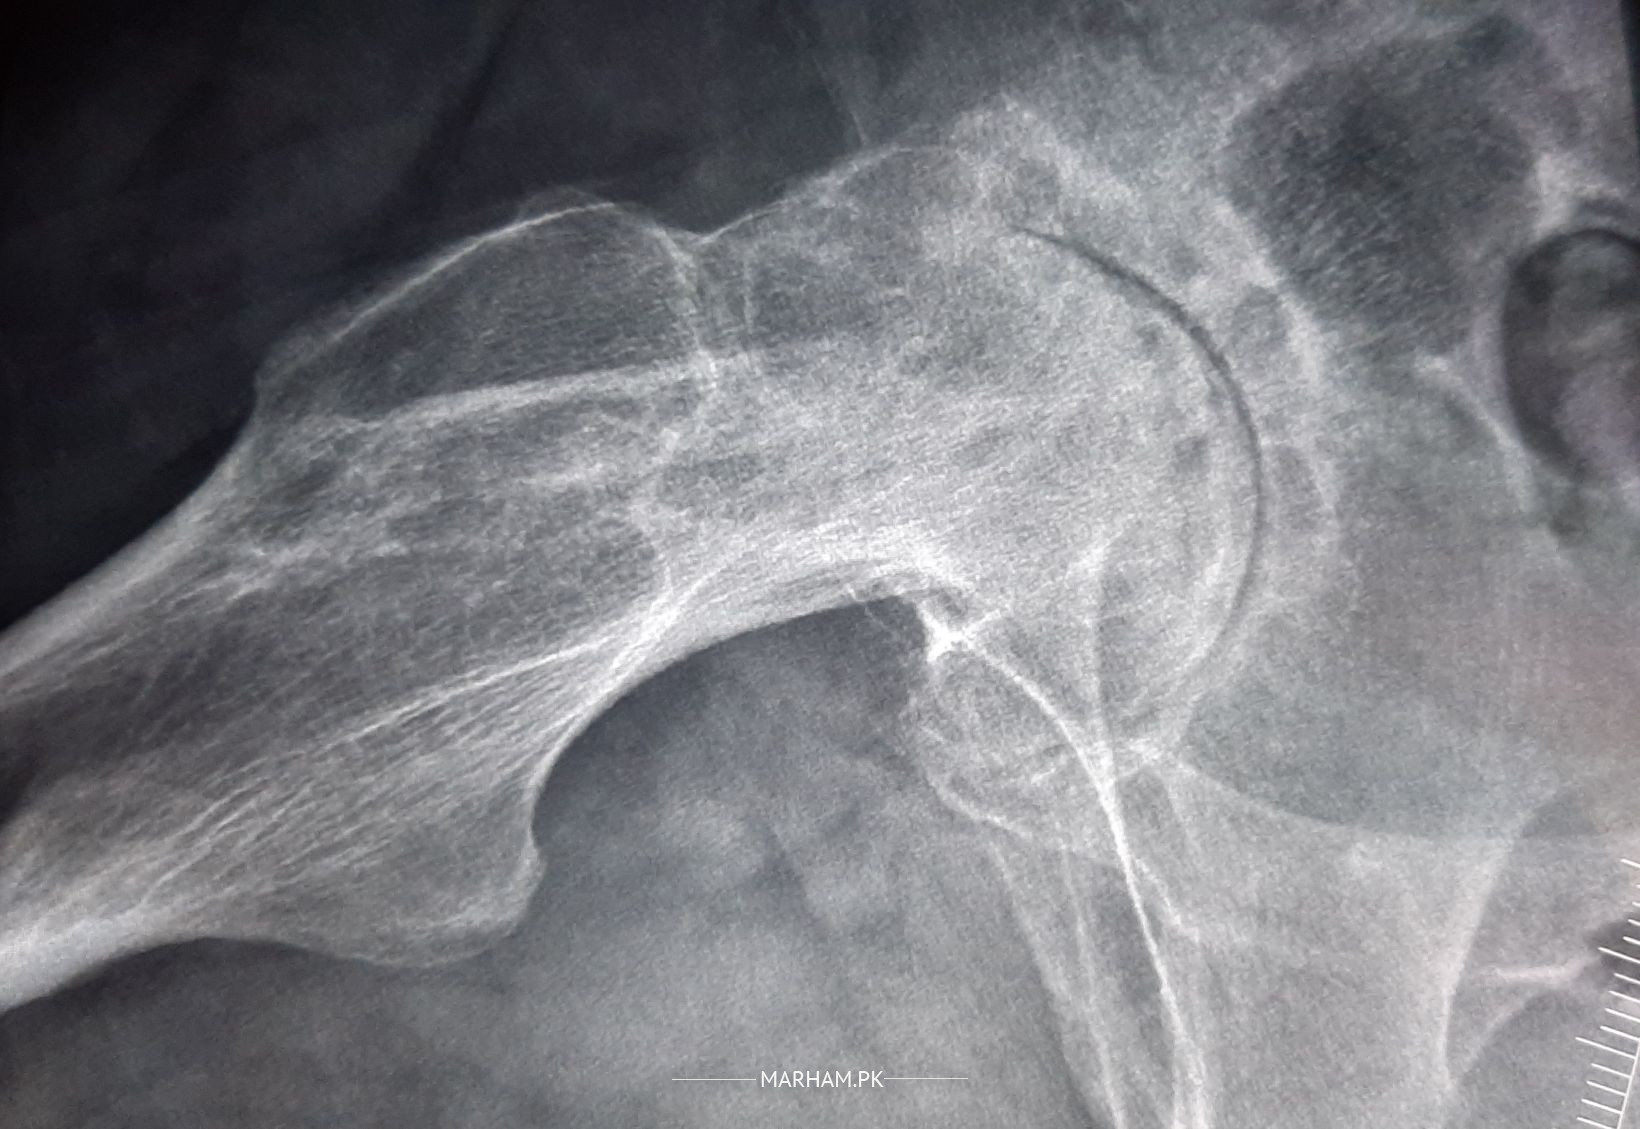

I'm 38 yrs old and was Diagnosed with Avascular Necrosis at the age of 27 because of excessive use of STEROIDS during meningitis. I had done with Bone Graffting (decompression) in both Hip Joints. Unfortunately, I had to go for Total Hip Replacement of my left joint. Now after almost 10 yrs, I am having pain in my Right Joint, it is not bearing my weight now. And when I walk my walk is not balanced. Having severe pain while walking and even a slight movement creates pain, that goes towards my knee. My X rays is attached. Need suggestions and recommendation.

Hello , Your rt hip also is not good condition. X-ray shows advanced degenerative changes , it also need total joint replacement . Try these medicine for 1 week . Tab Proxen 500 mg 1+0+1 , Tramapar 1+0+1 , cap Nexum 40 mg 1+0+0. then come for follow up . This is number of my PA 042-32591427, 98. In SouthCity Hospital

total hip replacement is best solution. don't delay too much. you already getting cystic bone changes in acetabulum as well. it's not good

you need un cemented hip replacement. the changes are Ficat4. nothing else will work